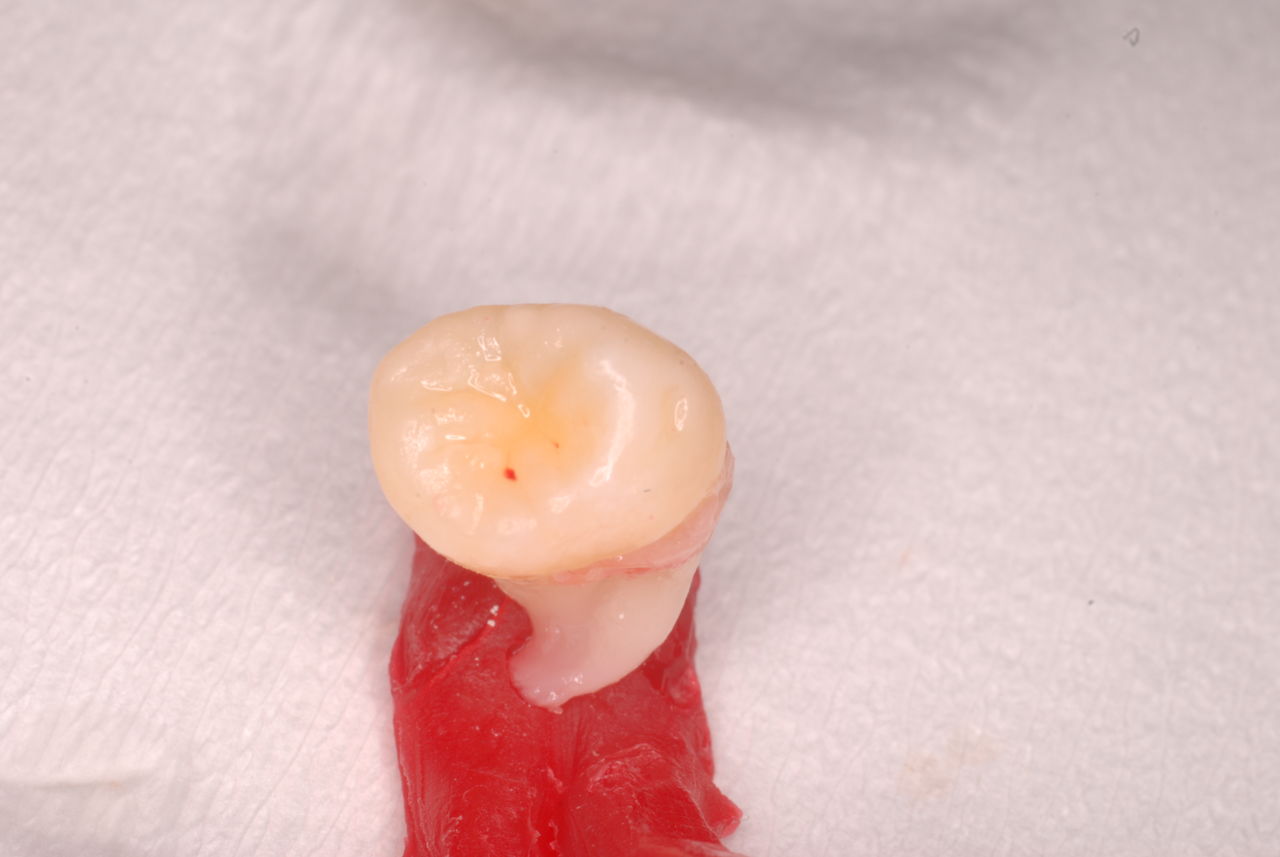

写真左下の親知らずが痛くなり抜歯しました。その後歯茎を除去して虫歯を露出させる処置を二回ほどしています。

レントゲンでは小さいですが、こう言う虫歯が一番怖いのです。

治療の成功率は極めて悪くすぐ再発しやすいのです。